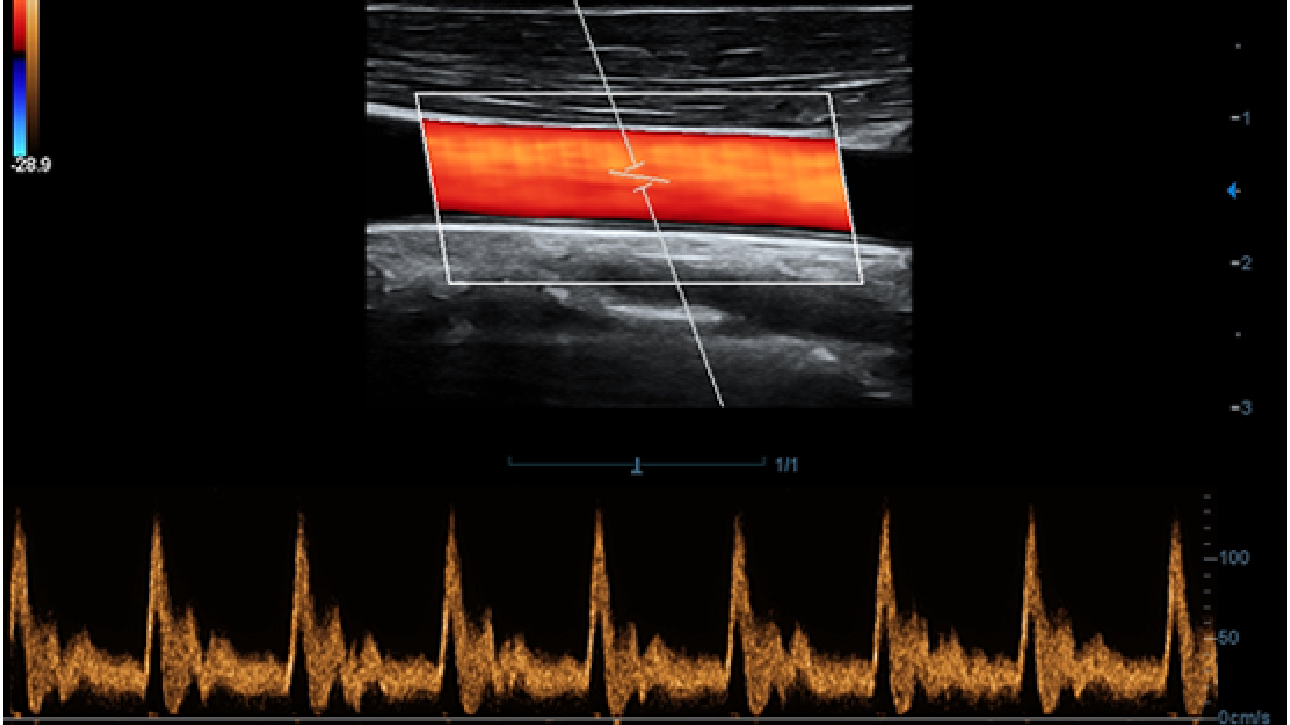

X-Insight ├© una soluzione completa studiata per offrire la migliore qualit├Ā diagnostica.

La nuova soluzione di Mindray ├© la traduzione pratica delle esigenze quotidiane dei clienti in soluzioni cliniche, il tutto con tecnologie ad ultrasuoni all'avanguardia ed in continua evoluzione.

Proponendosi come partner affidabile, DC-60 Exp con X-Insight si concentra su ci├▓ che conta veramente, semplificando la gestione della pratica clinica quotidiana con facilit├Ā e sicurezza.

Progettato per rispondere al meglio alle esigenze del cliente, DC-60 Exp con X-Insight ├© studiato per offrire un'efficienza elevata nel campo dell'imaging di precisione, grazie a una chiarezza immediata (eXpress Clarity), allŌĆÖeccezionale intelligenza (eXceptional Intelligence), oltre a vantare una lunghissima esperienza (eXceeding Experience).